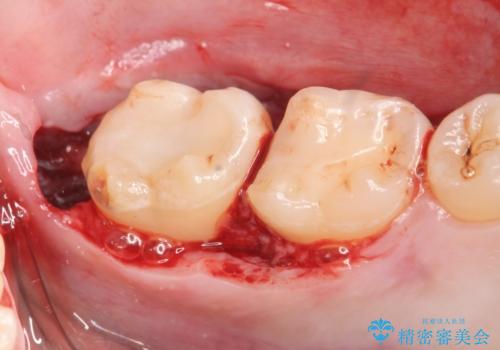

左下7の虫歯は深く、また歯冠高径も低かったため、歯冠長延長術を行いました。

歯冠長延長術について

歯冠長延長術とは歯肉弁根尖側移動術とも言い、歯の高さが低くクラウン(被せ物)による治療が難しい場合に、歯茎を歯根方向に下げることで歯の高さを確保する手術です。歯の高さが十分にあることで、外れにくいしっかりとしたクラウンを被せることができます。

虫歯が進み歯茎より深くなってしまうと、虫歯を取り残してしまうリスク、樹脂の硬化の妨げ、補綴物の不適合、歯肉炎・歯周病のリスクの増大等様々な弊害が起こり得ます。